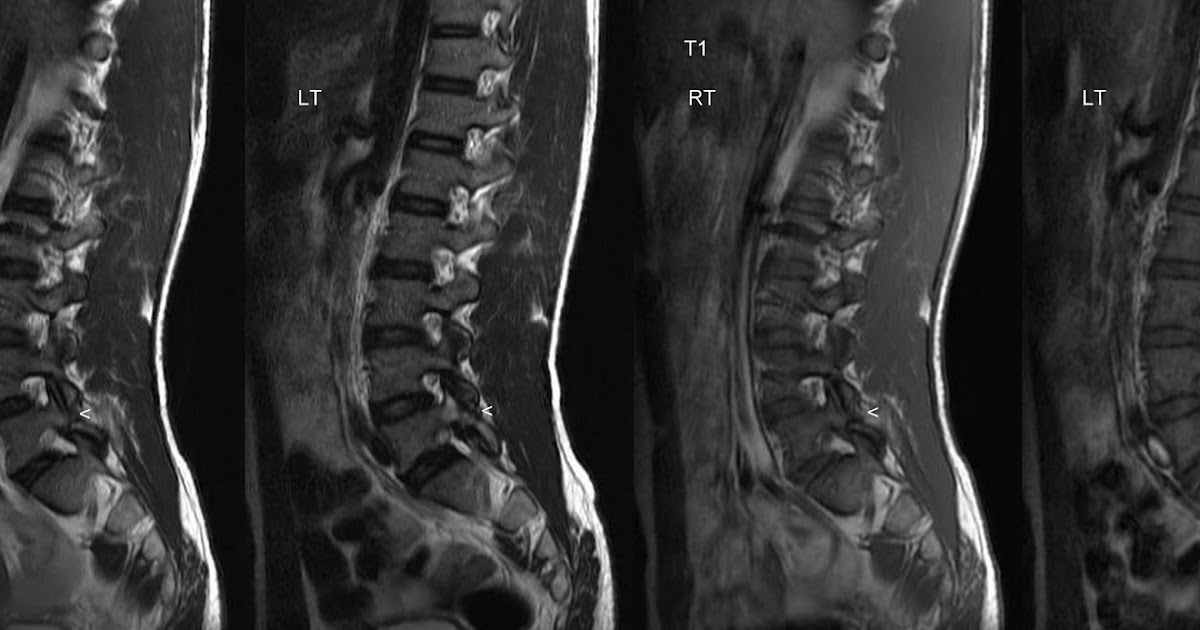

From www.neuroradiologycases.com

Neuroradiology Cases Spondylolysis Stress Fracture L5 The stress distribution at the pars interarticularis at its highest in extension and rotation movements. They're caused by repetitive force, often from overuse — such as repeatedly jumping up and down or running long distances. Spondylolysis is a stress fracture through the pars interarticularis of lumbar vertebrae. The most common presenting symptom of a stress fracture in the pars interarticularis. Stress Fracture L5.